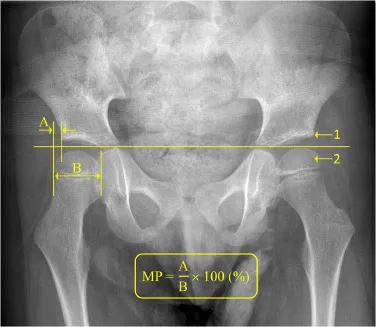

⭐ Reimer's Migration Percentage (MP) > 30% signals hip instability; >40% often warrants surgical intervention.